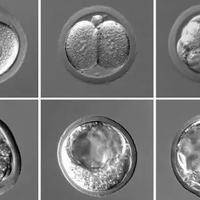

三代试管囊胚等级全知道:分几种?

嘿,朋友!如果你正在了解或考虑三代试管婴儿技术,那你肯定听过“囊胚等级”这个词儿。简单来说,三代试管就是在胚胎植入前进行遗传学诊断,确保宝宝健康的技术。而囊胚呢,是胚胎发育到第五六天的一个关键阶段,像个小气球一样,里面包着将来变成宝宝的细胞。这时候,医生们会给囊胚打分,也就是评定等级,这直接关系到试管婴儿的成功率。想想看,等级高的囊胚,植入后更可能顺利着床,帮你圆梦。所以,今天咱们就来聊聊,三代试...